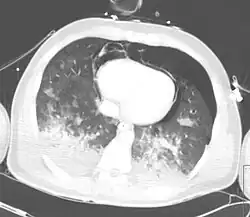

Severe pulmonary contusion with pneumothorax and hemothorax following severe chest trauma[75]

A large amount of force is required to cause pulmonary contusion; a person injured with such force is likely to have other types of injuries as well.[26] In fact, pulmonary contusion can be used to gauge the severity of trauma.[29] Up to three quarters of cases are accompanied by other chest injuries,[44] the most common of these being hemothorax and pneumothorax.[42] Flail chest is usually associated with significant pulmonary contusion,[18] and the contusion, rather than the chest wall injury, is often the main cause of respiratory failure in people with these injuries.[76] Other indications of thoracic trauma may be associated, including fracture of the sternum and bruising of the chest wall.[70] Over half of fractures of the scapula are associated with pulmonary contusion.[31] The contusion is frequently found underlying fracture sites.[40] When accompanied by a fracture, it is usually concentrated into a specific location—the contusion is more diffuse when there is no fracture.[35][48] Pulmonary lacerations may result from the same blunt or penetrating forces that cause contusion.[8] Lacerations can result in pulmonary hematomas; these are reported to develop in 4–11% of pulmonary contusions.[8]